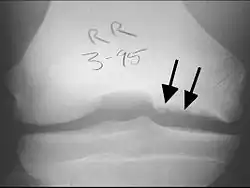

X-rays show lucency of the ossification on the anterior aspect of the knee in juvenile patients. In older people, the lesion typically appears as an area of osteosclerotic bone with a radiolucent line between the osteochondral defect and the epiphysis. The visibility of the lesion depends on its location and on the amount of knee flexion used. Harding described the lateral X-ray as a method to identify the site of an OCD lesion.[36]

CT scan and projectional radiography of a case of osteochondritis dissecans of parts of the superior-medial talus. -